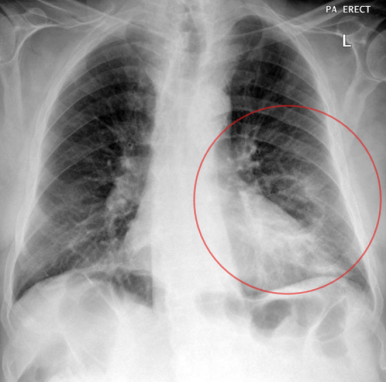

■ Cavitary lesion / nodule (공동성 병변)

§ Solitary cavitary nodules (단일 공동성 결절)

- 공동성 병변은 thick, irregular 한 wall

- 내부에 solid mural component가 존재할 수도 있음.

- 벽의 두께에 따라 4mm 이하 = benign, 15mm 이상일 경우 malignant의 가능성이 높음

- Spiculated(침상형)의 경계를 가질경우 malignant의 가능성 높음

→ ADC와 SCC 모두 공동을 형성 할수 있으나, SCC에서 더 흔함. SCLC는 공동 형성 X